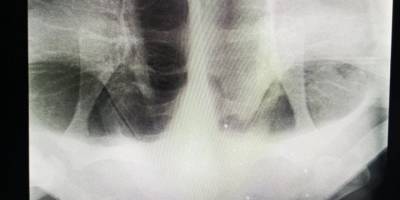

İzmir'de tedavi altına alınan caretta carettanın ateşli silahla vurulduğu belirlendiİzmir'de tedavi altına alınan caretta carettanın ateşli silahla vurulduğu belirlendiOğuz'un haber vermesi üzerine bölgedeki bir balıkçı teknesi yaralı deniz kaplumbağasını tedavi ettirmek için çıkarmaya çalıştı ancak başarılı olamadı.